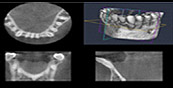

通常のレントゲンでは確認できない、顎の骨の状態を細部まで3次元の立体で確認する事ができます。治療を行う前だけではなく、治療終了後にも撮影を行い状態を把握します。

一歯科用CT(ヨシダ トロフィーパンプラス)にてアゴの骨の立体的な形態や、神経の位置把握、さらに骨密度の診査などを調べます。デジタルにより従来のフィルムを使用したレントゲン撮影に比べ、人体に受ける放射線の量を約1/4〜1/10に抑える事が可能に、またCT(3D)機能により断層写真、立体的な撮影ができますので、インプラントのみならず、あらゆる歯科診療でより正確な診断と正確な治療が行えます。

CTによる3次元画像により、通常のレントゲン写真ではわからなかった部分が、精密・立体的に見ることができ、インプラント治療の精度も飛躍的に向上します。